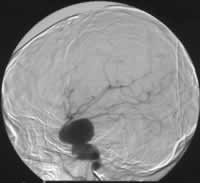

近日,重庆第三军医大学西南医院神经外科采用颅内外动脉搭桥术结合血管内介入栓塞术成功治愈1例颈内动脉海绵窦段巨型梭形动脉瘤。该患者年仅10岁,经检查发现其动脉瘤直径超过4 cm,且合并基底动脉闭塞,颅内血供仅靠双侧颈内动脉维持。经过认真讨论后,专家们利用截取的患者自体桡动脉,成功地将颞浅动脉与大脑中动脉搭桥连接。1周后,脑血管造影显示患者颅内外血管通畅,专家遂实施介入手术,对患侧颈内动脉进行血管内栓塞。患者术后恢复良好,生命体征平稳,已康复出院。, http://www.100md.com